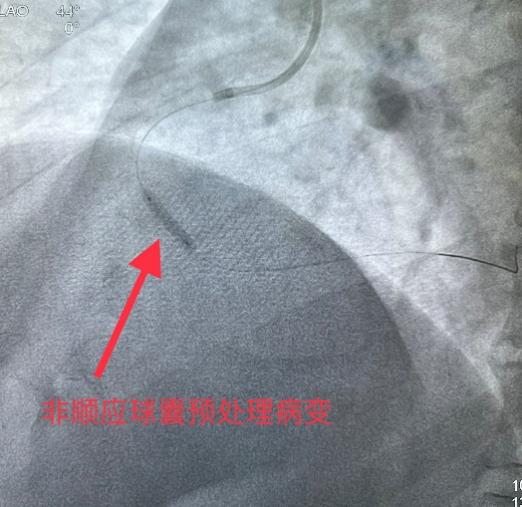

5月31日经过充分的术前准备,雷新军教授带领景林德博士和李瑞峰医生按照预定方案为患者实施了手术。冠脉造影示:RCA 2段节段性狭窄约25%,末端狭窄约90%,为不稳定斑块,血流TIMI 3级(图2a)。决定干预右冠:6F SAL1.0指引导管到位后,先操控Sion导丝通过病变至LV末端,然后再沿导丝送入血管内超声(intravenous ultrasound,IVUS)检查,结果显示RCA 2段末狭窄最重部位血管面积为2.30 mm2,斑块负荷为85%,手术指征明确(图2b)。首先,使用NC Balloon 3.0 x 15 mm 20 atm预扩张靶病变,造影示残余狭窄约25%,再在IVUS指导下植入Xinsorb BRS 3.5 x 28 mm,随后采用NC Balloon 3.5 x 9 mm 16atm逐段后扩张,造影显示支架充分膨胀,血流TIMI 3级(图2c-g)。最后,进一步使用IVUS评估手术情况,结果显示:支架充分膨胀,贴壁良好,支架远近端未见夹层,血管面积为8.01 mm2,手术效果非常满意(图2h)。术中患者无特殊不适,术后病人安返病房。

图2 经皮冠脉介入治疗